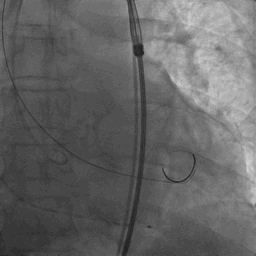

TaurusOne®轻松过弓

TaurusOne®释放过程:

瓣膜定位

瓣膜释放

瓣膜释放后

瓣膜释放后形态位置良好,造影无返流。